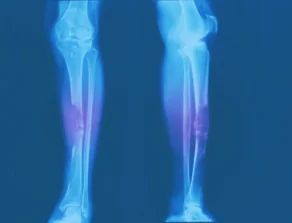

Bone Cancer

- Bone pain that becomes constant over time and worsens with activity.

- Swelling near pain area that happens later; may feel lump depending on location

- Bone cancer most of the time does not fracture; Feeling sudden bone pain after soreness for months may indicate a fracture.